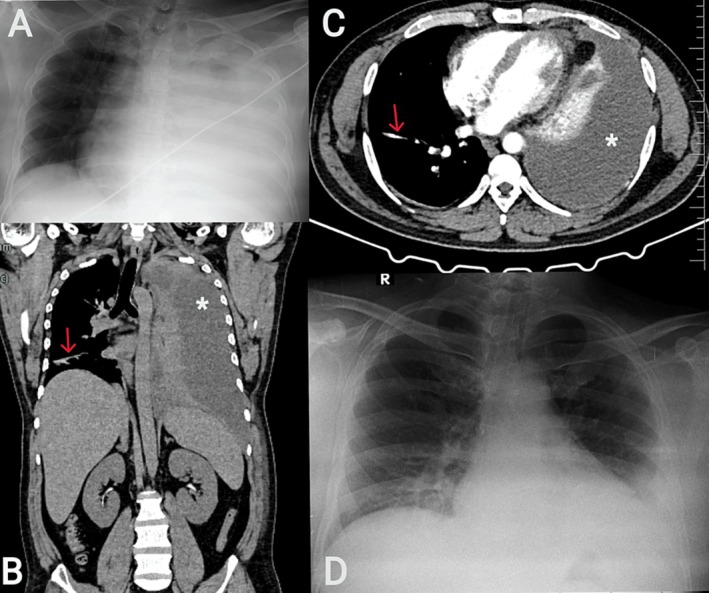

乳糜胸的特点是乳糜积聚在胸膜间隙,是一种罕见但临床意义重大的疾病。这种淋巴液富含从肠道吸收的脂肪,可由各种因素引起,包括创伤、恶性肿瘤和肺结核(TB)。创伤原因,特别是医源性手术,占病例的很大比例,其次是罕见的病因,如恶性肿瘤,如淋巴瘤,以及不太常见的结核病。在前两例中,患者在乳糜胸检查时被诊断为结核病;然而,在第三例中,患者发展为乳糜胸作为套细胞淋巴瘤(MCL)的并发症。2例男性患者,年龄分别为43岁和45岁,表现为呼吸道症状和乳白色胸腔积液(甘油三酯> 180 mg/dL)。在这两例患者中,支气管肺泡灌洗证实为利福平敏感性结核。两例患者均对抗结核治疗和饮食调整有反应。69岁男性,有非霍奇金淋巴瘤病史,乳糜胸(甘油三酯286 mg/dL)和淋巴结病变;影像学和活检证实MCL。他对化疗有反应。这一系列强调了在评估和根据特定病因定制治疗时考虑乳糜胸不常见原因的重要性。

Chylothorax, characterised by the accumulation of chyle in the pleural space, is a rare yet clinically significant condition. This lymphatic fluid, rich in fats absorbed from the intestine, can be caused by various factors including trauma, malignancy, and tuberculosis (TB). Traumatic causes, particularly iatrogenic procedures, account for a significant proportion of cases, followed by rare etiologies like malignancies such as lymphoma, and less commonly, tuberculosis. In the first two cases, the patient was diagnosed with tuberculosis during evaluation for chylothorax; however, in the third case, the patient developed chylothorax as a complication of mantle cell lymphoma (MCL). Two male patients, aged 43 and 45, presented with respiratory symptoms and milky pleural effusions (triglycerides > 180 mg/dL). In both, bronchoalveolar lavage confirmed rifampicin-sensitive TB. Both patients responded to anti-tubercular therapy and dietary modification. A 69-year-old male with a history of non-Hodgkin's lymphoma developed chylothorax (triglycerides 286 mg/dL) and lymphadenopathy; imaging and biopsy confirmed MCL. He responded to chemotherapy. This series underscores the importance of considering uncommon causes of chylothorax during evaluation and tailoring treatment based on specific etiologies.